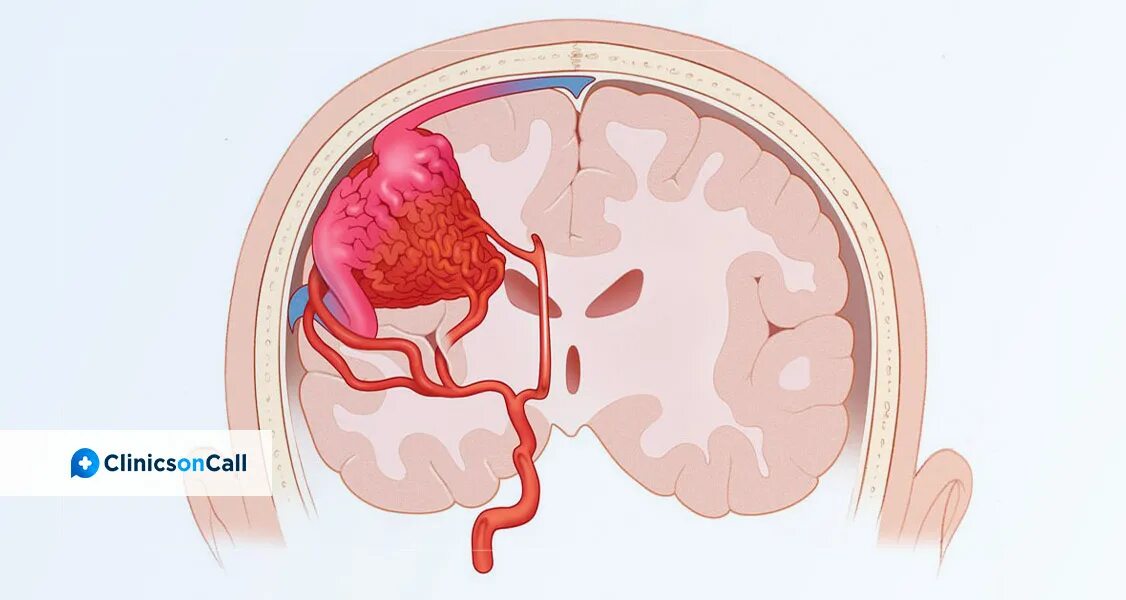

Что такое мальформация головного мозга